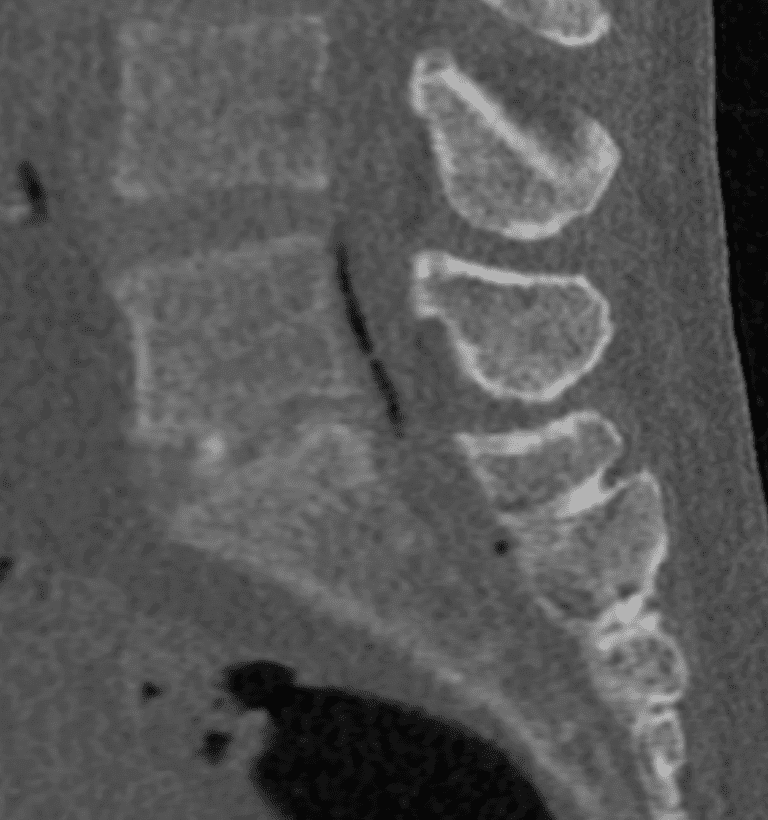

Préparation et imagerie préopératoire

Une imagerie (scanner ou IRM) est réalisée en amont pour établir le diagnostic, évaluer l’anatomie discale et planifier la trajectoire d’insertion.

Un contrôle imagerie est effectué en fin d’intervention pour vérifier la qualité de la décompression et la bonne répartition des espaces discaux, garantissant ainsi l’efficacité du geste.